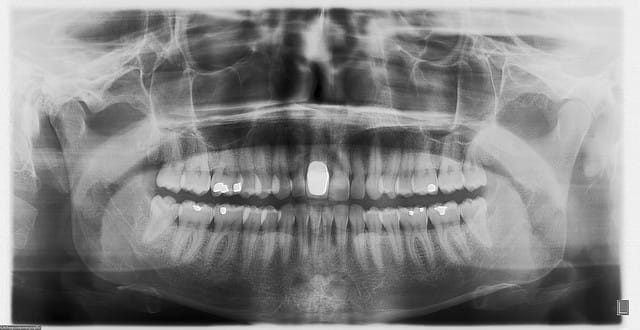

11 avec résorption interne

EII avec MCI sur du dentium (4.5/14) comblement du gap vestibulaire avec du kasios tcp (très constant dans les résultats...et très économique)

pas de photos de chir par contre...j'ai du les effacer par erreur...grrrr...

la prothèse d'usage a été réalisée par ma petite associée...mais j'étais là pour superviser et faire quelques photos...;-)